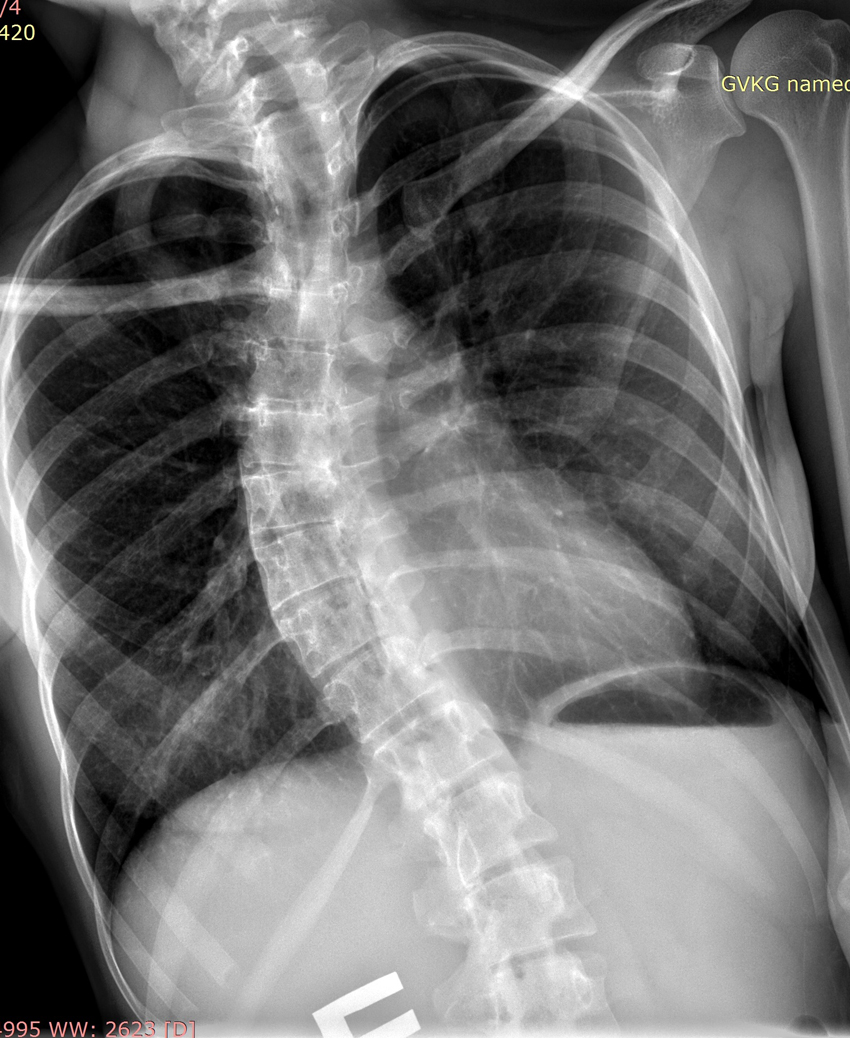

- рентгенографию;